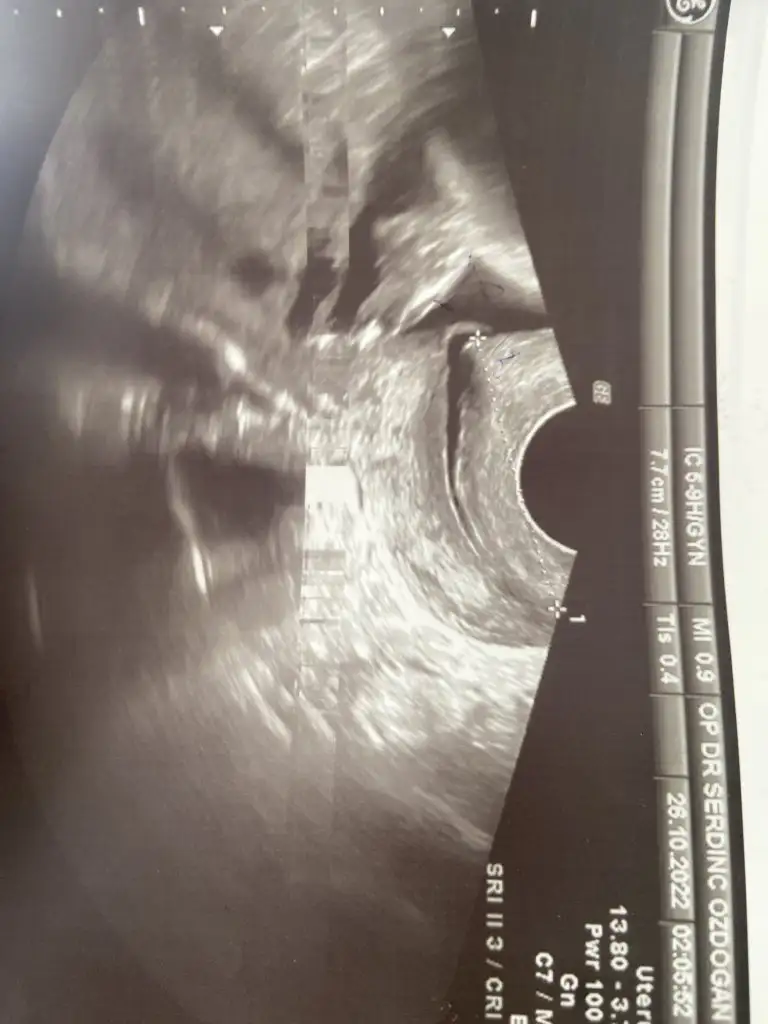

Kızlar şimdi çıktım doktordan Altan baktı rahimde içerden hafif açıklık var dedi bebeğin başıda Rahime baskı yapıyor evet aşağıda bebek dedi. Ama rahim yapında böyle olabilir bazen doğuma kdar böyle gidenler var haftaya gel mutlaka kontrol edelim dedi. Magnezyum ve kalsiyum verdi. O açıklığı kontrol edeceğiz dedi o yüzden haftaya çağırdı. Dinleneceksin çalışmayacaksın dedi.. Rahim filmini de yolluyorum şimdi. Bilmiyorum böyle bişey yaşayan oldu mu. Stres yaptım ister istemez. Doktorum stres yapma dedi. Ama erken doğum riski bunlar. Daha da çok erken Yeni girdim 6.ayıma.. sürekli aşağıda bebek. İnşallah yapısıyla alakalıdır. Ne diyim bekleyeceğiz işte 1 hafta.Yoktur Allahın izniyle bende de oluyor alta toplanıyor bazen kasılıyor

cok gecmiş olsun. açıklık nasıl olabilir onu anlayamadım. içeride dedigine göre rahim ağzı kapalıdır herhalde, onunla ilgili olsa eve göndermezdi. zaten doğuma kadar böyle gidenler var demiş. doktoru dinle bol bol yat dinlen canım, Allah ın izniyle sağlıkla tamamlayacaksın hamilelik sürecini, zaten gözlemleyecegiz demiş. naçizane tavsiyem uzun süre ayakta kalma, eğilip çömelme hareketlerinden kaçın, kabız olmamaya dikkat et. iyi düşün, moralini yüksek tut, doktorunla da irtibat halinde ol farklı bir durum olursa.Kızlar şimdi çıktım doktordan Altan baktı rahimde içerden hafif açıklık var dedi bebeğin başıda Rahime baskı yapıyor evet aşağıda bebek dedi. Ama rahim yapında böyle olabilir bazen doğuma kdar böyle gidenler var haftaya gel mutlaka kontrol edelim dedi. Magnezyum ve kalsiyum verdi. O açıklığı kontrol edeceğiz dedi o yüzden haftaya çağırdı. Dinleneceksin çalışmayacaksın dedi.. Rahim filmini de yolluyorum şimdi. Bilmiyorum böyle bişey yaşayan oldu mu. Stres yaptım ister istemez. Doktorum stres yapma dedi. Ama erken doğum riski bunlar. Daha da çok erken Yeni girdim 6.ayıma.. sürekli aşağıda bebek. İnşallah yapısıyla alakalıdır. Ne diyim bekleyeceğiz işte 1 hafta.